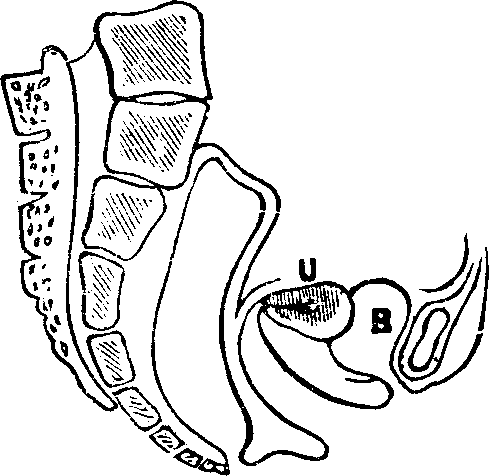

Fig. 10. Flexion, u, Uterus, B, Bladder.

Flexions and Versions of the Womb. Flexion of the uterus, in which it is bent upon itself, as illustrated in Fig. 10, produces a bending of the cervical canal, constricting or obliterating it, and thus preventing the passage of spermatozoa through it. Version of the uterus [pg 710]in which its top, or fundus, falls either forward against the bladder (anteversion), as illustrated in Fig. 11, or backward against the rectum (retroversion), may close the mouth of the uterus by firmly pressing it against the wall of the vaginal canal, and thus prevent the passage of spermatozoa into the womb. 'The treatment of these several displacements will be considered hereafter. We may here remark, however, that they can be remedied by proper treatment. Our mechanical movements, manipulations, and kneadings are invaluable aids in correcting these displacements.